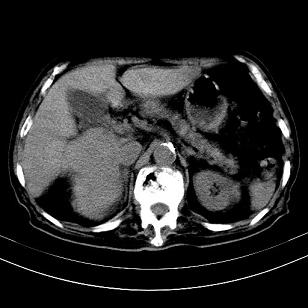

标题: CT19407:肝内还是肝外原发性肿瘤??

男,63岁,高血压病史40余年,

来源-右侧肾上腺。

考虑右侧肾上腺巨大占位;恶性?

肝内多发低密度找;转移瘤?

另:右肾结识,多发小囊肿。

考虑右肝后叶肝癌(部分外生)伴肝内多发性转移;右侧肾上腺区恶性肿瘤并肝转移待排。

考虑右侧肾上腺肿瘤并肝内多发转移。右侧肾上腺呈“八”字形,包括内侧枝及外侧枝,内侧枝受压,考虑外侧枝原发肿瘤。”

考虑肝右后叶肝癌(部分外生)伴肝内多发性转移;不排除右侧肾上腺区恶性嗜铬细胞瘤并肝转移。